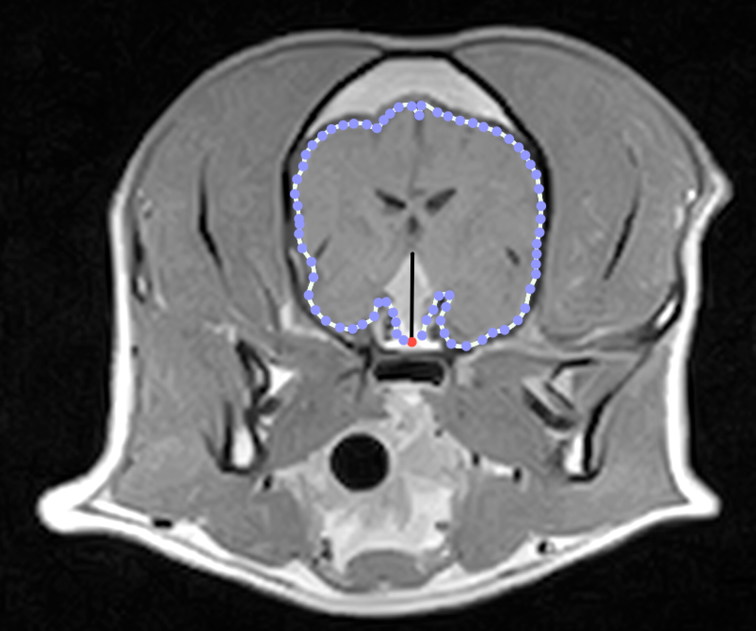

If CDI is diagnosed, MRI or CT scan of the brain is recommended to evaluate for pituitary masses. Up to 40% of dogs with CDI have an underlying pituitary tumor.

Figure 2: Transverse post-contrast T1-W MR image of the brain from a dog with a DPM.

Reference: Menchetti M, De Risio L, Galli G, Bruto Cherubini G, Corlazzoli D, Baroni M, Gandini G. Neurological abnormalities in 97 dogs with detectable pituitary masses. Vet Q. 2019 Dec;39(1):57-64. doi: 10.1080/01652176.2019.1622819. PMID: 31112462; PMCID: PMC6831018.

- Figure 3 - Pituitary MRI: PMC Open Access - Menchetti M, De Risio L, Galli G, Bruto Cherubini G, Corlazzoli D, Baroni M, Gandini G. Neurological abnormalities in 97 dogs with detectable pituitary masses. Vet Q. 2019 Dec;39(1):57-64. doi: 10.1080/01652176.2019.1622819. PMID: 31112462; PMCID: PMC6831018.